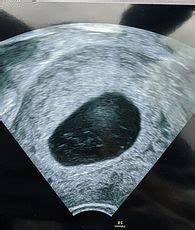

So, what actually happens during your 20-week scan? You’ll usually lie down on an examination bed, and a sonographer will apply a clear, warm gel to your abdomen. This gel helps the ultrasound probe (a transducer) to slide smoothly over your skin and transmit clear sound waves. The probe is then moved gently across your belly, and the ultrasound waves create images of your baby on a monitor. The sonographer will systematically examine different parts of your baby’s body. They’ll measure the baby’s head, abdomen, and thigh bone, check the spine, heart, brain, kidneys, stomach, and bladder, and look at the placenta and the amount of amniotic fluid. They’ll also check the umbilical cord. You’ll likely see your baby moving around, maybe kicking or stretching! It’s a pretty amazing experience. You’ll have the opportunity to ask questions during the scan, and the sonographer will explain what they are seeing. If they identify anything that concerns them, they will discuss it with you and explain the next steps, which might involve further scans or consultations with a specialist. Try to relax and enjoy seeing your little one. Deep breaths can help if you’re feeling anxious. Remember that the sonographer is a trained professional whose job is to conduct this thorough examination. They will provide you with clear information about what they find. Sometimes, it can be a little tricky to get a clear view of certain parts of the baby, especially if they are in an awkward position or if there’s a lot of movement. The sonographer might ask you to move around, cough, or even have a sugary drink to encourage the baby to shift position. It’s all part of the process to get the best possible images for a comprehensive assessment. The entire process usually takes between 20 to 40 minutes, depending on how cooperative the baby is!